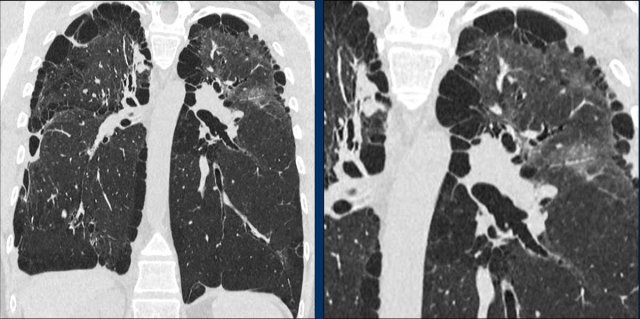

These images are of a 65-year-old woman with dyspnoe and a history of smoking.

Findings

There are thin-walled cysts within areas of ground glass and subtle fibrosis.

Notice the traction bronchiectasis (arrow).

Continue with more images of this patient...

The main differential diagnosis of pulmonary cysts in combination with ground-glass is DIP and LIP.

The most likely diagnosis is DIP, because the patient is a smoker and because the cysts are only located within areas of ground glass.

DIP cysts are located in the periphery of the lower lung fields and frequently combined with fibrosis.

DIP can also have a diffuse distribution.

This case is an example.